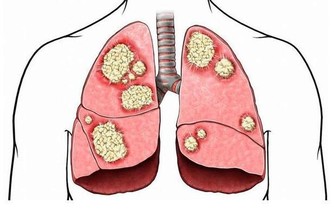

胸悶難受,試試按摩這裡

相信很多人都遇到過胸悶的情況,

一般大家都不會太在意,偶爾一兩次也不會用藥物治療,而是讓它自行消失。

但是,在發生胸悶的時候還是很難受的。